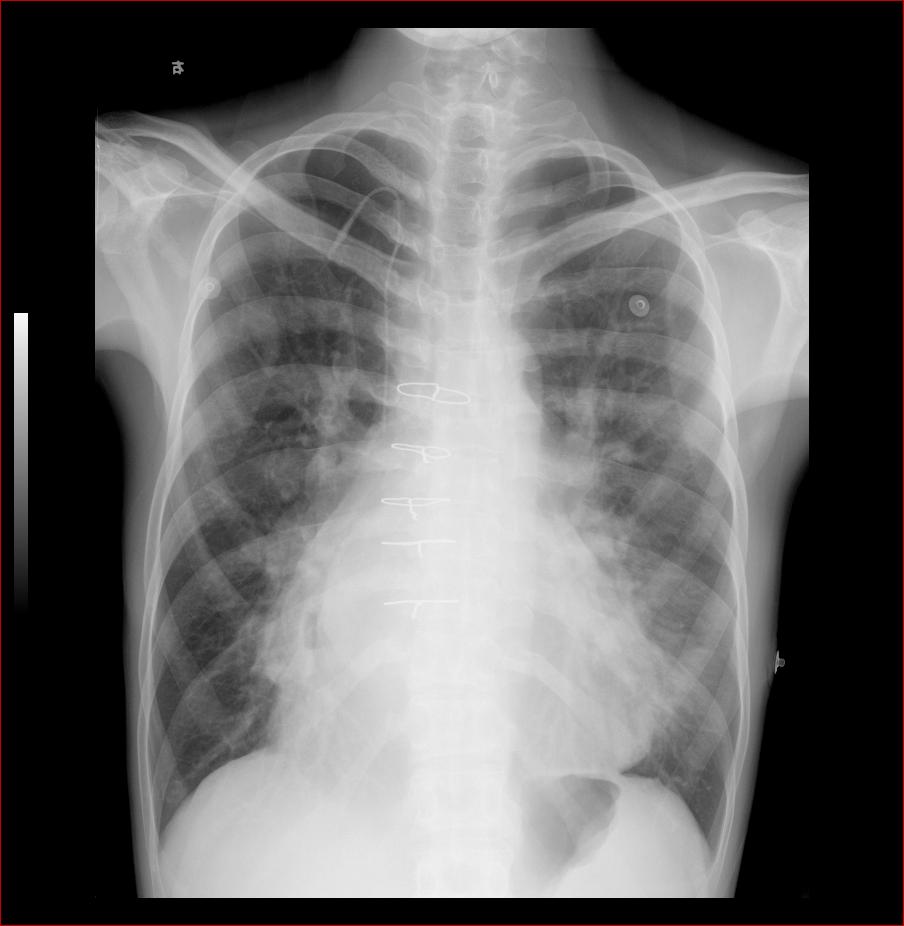

先天性心脏病、房间隔缺损

男31岁,心悸,气短

术后复查:

:主动脉结小,肺动脉突出,左心缘圆隆,右心房/心高值大,未见双房影,双肺呈多血改变,右下肺动脉宽。

符合先心病。心房间隔缺损。建议心彩。

结果

:患者既往彩超检查诊断,先心房缺